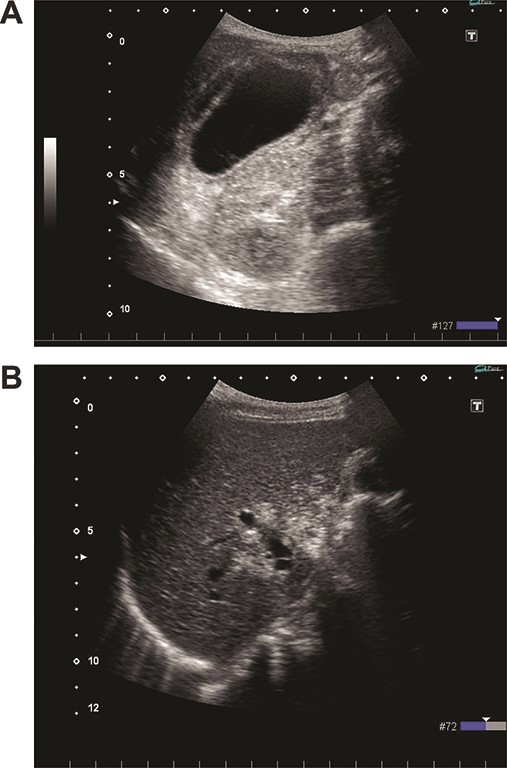

On admission, her vital signs were normal. Her medical history included dermatomyositis, hypertension and osteoporosis. She had a white blood cell count of 10.6 × 103/μL, hemoglobin of 8.2 g/dL and lactic acid of 0.8 mmoL/L. A physical examination demonstrated strong tenderness in her right upper quadrant abdomen. Ultrasonogramphy (US) showed diffuse wall thickening of her gallbladder without cholecystolithiasis. US also revealed small mobile echogenic foci moving inside the portal venous branches (Fig. 1). The hyperechogenic foci were seen in the middle segment and right anterior segment of the liver. Contrast-enhanced computed tomography (CT) showed a diffusely thickened wall of the gallbladder with poor enhancement, suggesting acute necrotizing cholecystitis (Fig. 2). Tiny bubbles were seen in the intrahepatic portal venous branches (segment 4 and segment 5), but there was no evidence of bowel ischemia. She was then diagnosed with necrotic cholecystitis and immediately underwent emergency operation.

(A) Abdominal CT shows a poorly enhanced and thickened wall of the gallbladder. (B) Abdominal CT shows tiny bubbles in the intrahepatic portal venous branches.